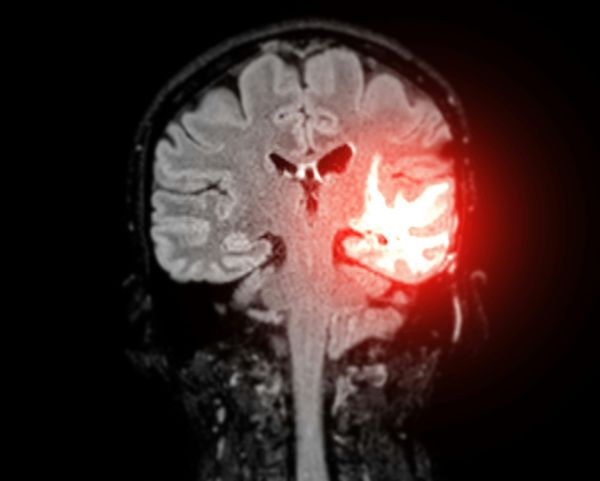

폐암 진단 및 추적을 위한 자동화 RECIST 기술 with Multi-Time Point Segmentation

포스트 코로나 이후 최근까지 폐 건강에 대한 관심이 크게 증가하고 있습니다. 이러한 현상은 폐암, 만성 폐쇄성 폐 질환(COPD), 천식, 폐 섬유증과 같은 폐 관련 질환의 증가와 밀접하게 관련되어 있습니다. 폐 질환의 증가는 전 세계적으로 수많은 사망 원인과 장기적인 건강 문제를 발생시키고 있습니다. 이에 따라 폐 건강에 대한 연구와 치료